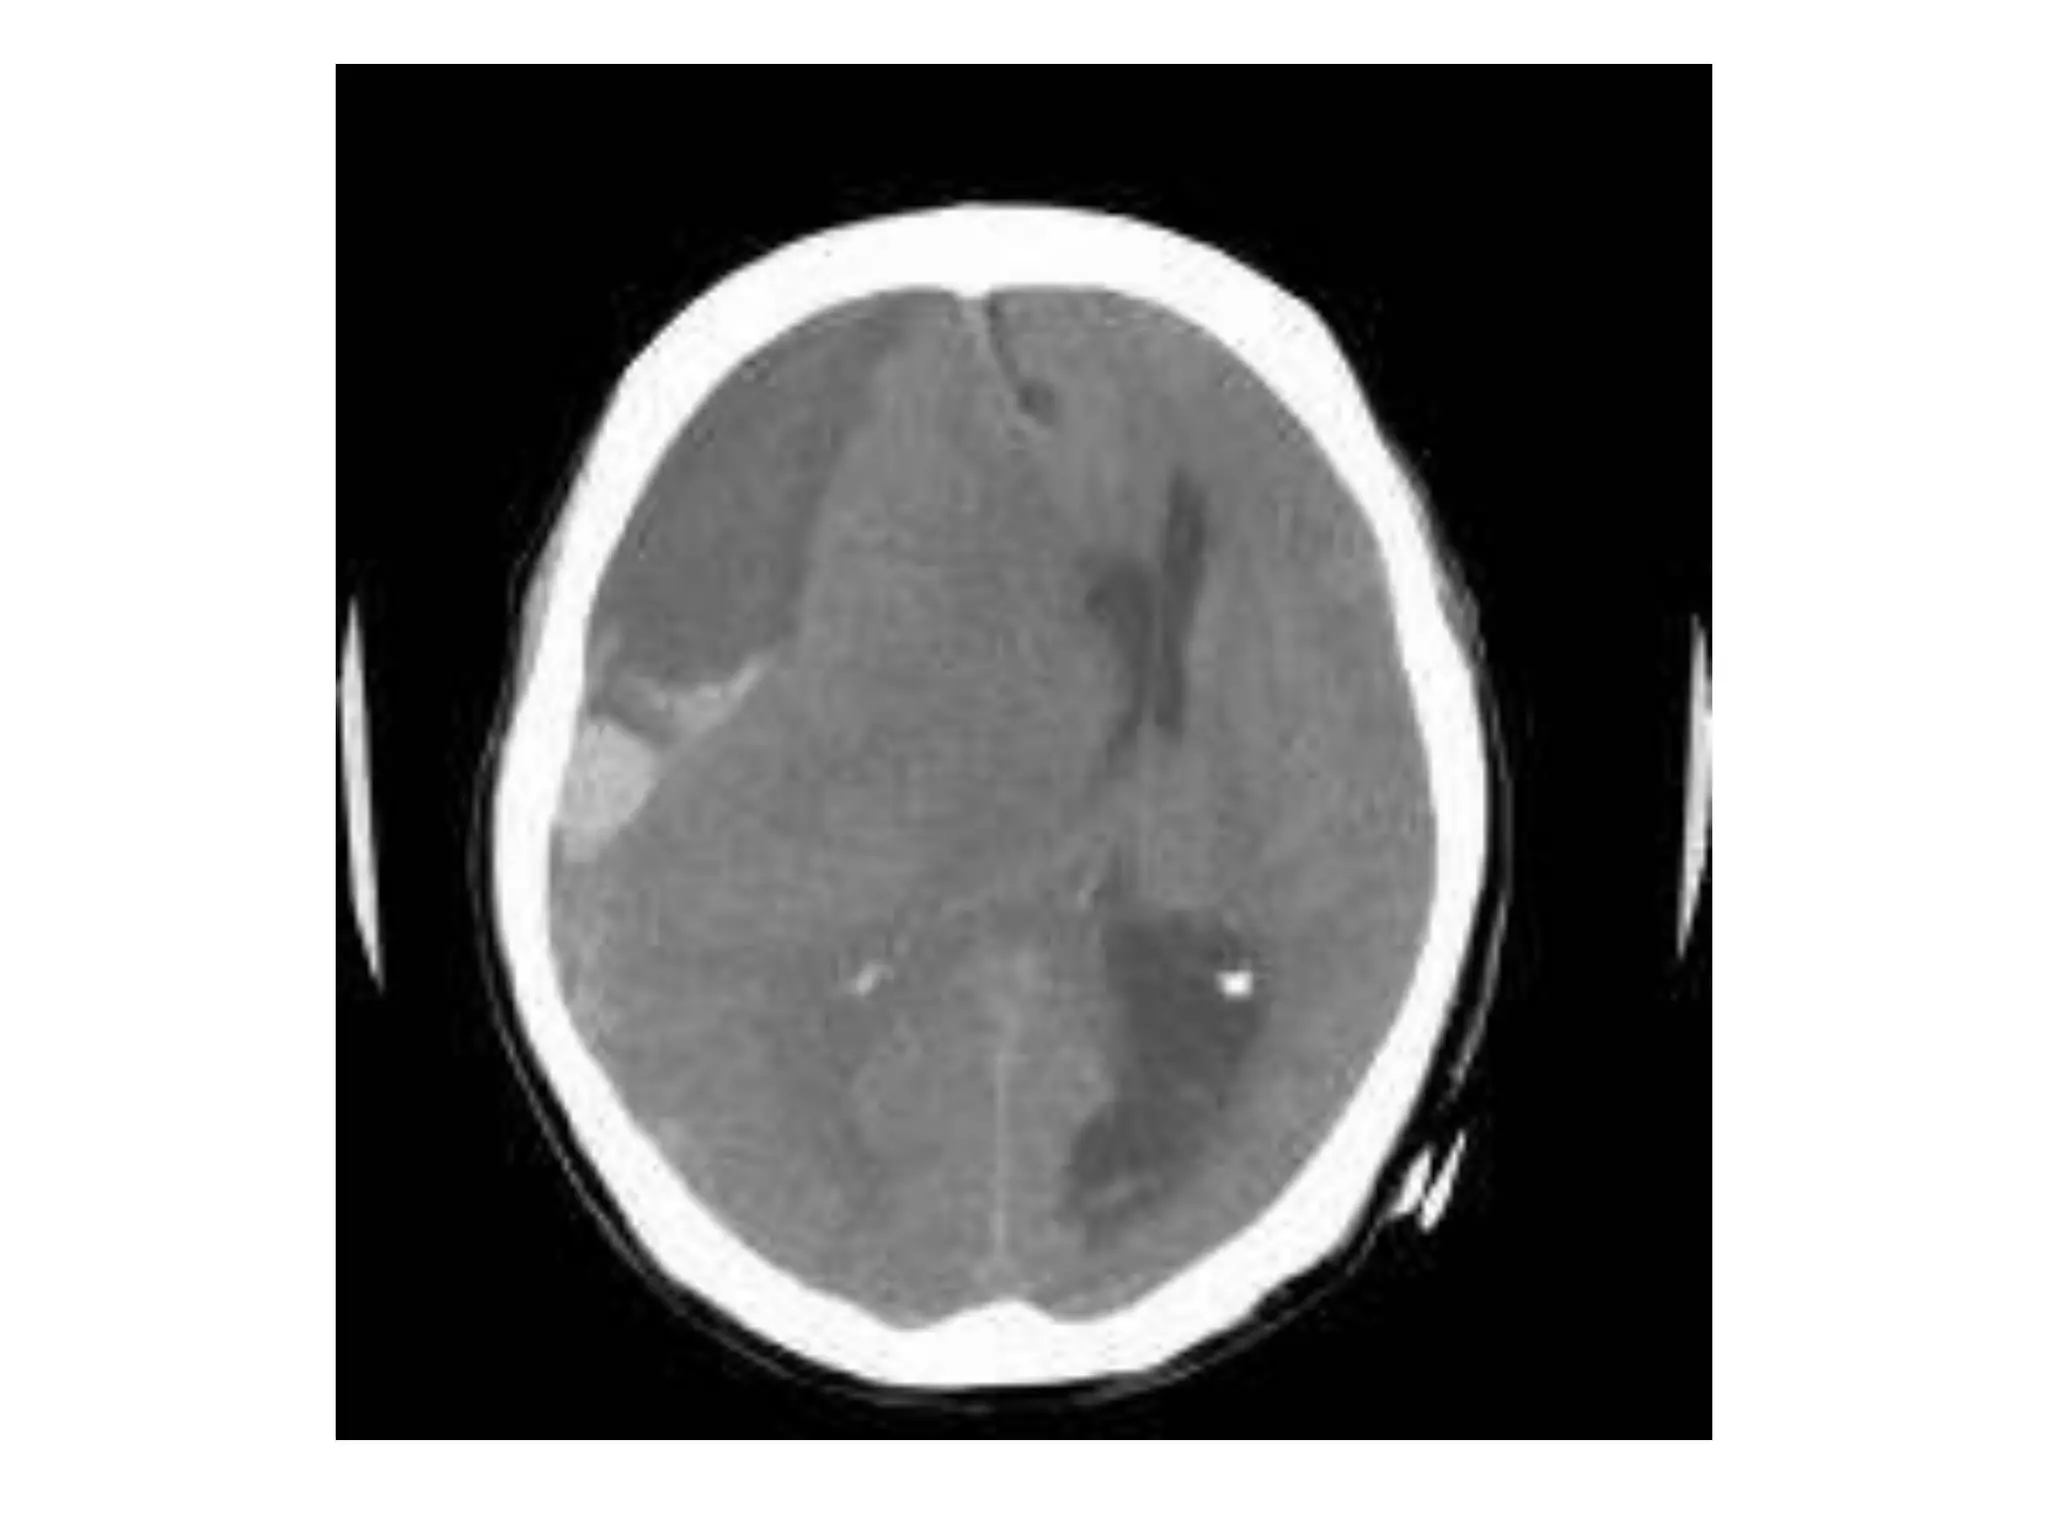

Etiologies of increased intracranial

1.VASCULAR:-

ICH with mass effect,

Epidural haemorrhage with mass effect,

SAH,

Large hemispheric stroke with mass effect,

Venous thrombosis,

Jugular vein ligation (radical neck dissection),

SVC syndrome